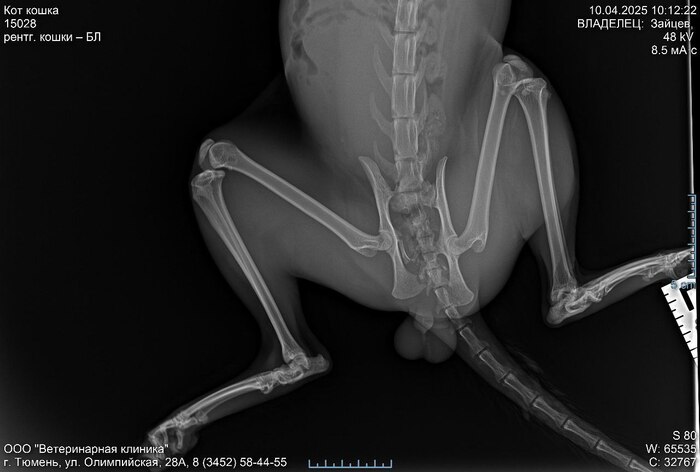

Полюбил его как сыночка, и назвал его Хосе - Прочитал в дзене значения имени, и показалось, что это имя "Бог да умножит" подходит точно. Решил я его не кастрировать после этого, такое хозяйство жалко губить. В итоге сейчас мы с ним лечимся, я лечу его а он меня, сегодня пойдем к лучшему в городе офтальмологу, у будет понятно возможно ли спасти глаз, операция на таз стоит около 35000 рублей. Сейчас я уже потратил свои ресурсы, и даже ресурсы соседей. Поэтому если кто-то желает помочь @ Tip9991 - это мой ник в телеграмм. Очень хочется чтобы эта тигра как раньше стал активным уличным котом, кстате незнаю от куда у него такая привычка что даже когда сильно нервничает и орёт, например, в ветеринарке. Когти не вытаскивает, и не кусается один раз только чуть чуть прикусил кофту, и сразу отпустил. Если кто-то всё же решится помочь я предоставлю все док-ва, которые вам нужно, вплоть до видеозвонка. А оставшийся средства отправлю на лечение другому коту, поэтому сильно не ругайтесь если не хотите, можете от...сосить меня в коментах панамку приготовил : )